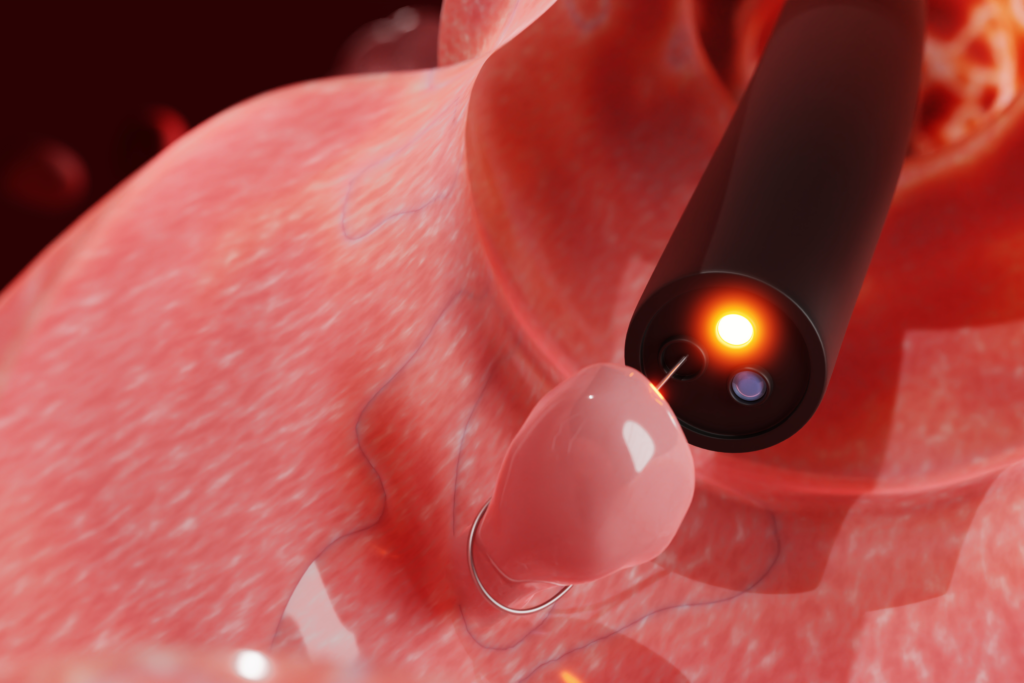

Endoscopie vétérinaire : comment ça marche ?